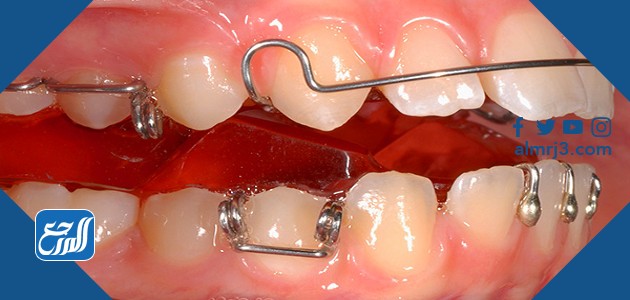

جهاز توسيع الفك العلوي هو عبارة عن جهاز معدني له مفتاح في المنتصف للتوسيع والتضيق، ويتم تركيب الجهاز في منتصف حلق المريض العلوي وتخرج منه أذرع معدنية إلى الأسنان والضروس المقابلة والتي تكون غير منتظمة الشكل وتحتاج إلى تقويم، ومع مرور الوقت يتم توسيع الجهاز بمعدل معين غالبًا ما يكون 1 ملي في كل شهر ليساعد في إعادة الأسنان إلى مواضعها الطبيعية، وفيما بعض تجارب الأشخاص الذين قاموا بتركيب الجهاز على أسنانهم العلوية:

- الجهاز رباعي المسامير ويعد من أكثر الأجهزة التي تستعمل بكثافة في علاج مشكلات الفم والأسنان.

- جهاز تمديد الفك العلوي وهو جهاز يتم تركيبه على الأسنان ليقوم بتحريك الأسنان التي نمت في المكان الخاطئ ومن ثم يعطي الفرصة للأسنان السفلية للظهور في مكانها الأصلي.

- جهاز توسيع الأسنان والذي يستخدم عندما تكون الأسنان متراكبة بعضها فوق بعض لا سيما الأسنان الأمامية فيعمل الجهاز على إعادة كل سن إلى مكانه الطبيعي.